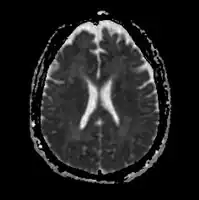

The diagnosis of hepatic encephalopathy can only be made in the presence of confirmed liver disease (types A and C) or a portosystemic shunt (type B), as its symptoms are similar to those encountered in other encephalopathies. To make the distinction, abnormal liver function tests and/or ultrasound suggesting liver disease are required, and ideally a liver biopsy.[3][8] The symptoms of hepatic encephalopathy may also arise from other conditions, such as bleeding in the brain and seizures (both of which are more common in chronic liver disease). A CT scan of the brain may be required to exclude bleeding in the brain, and if seizure activity is suspected an electroencephalograph (EEG) study may be performed.[3] Rarer mimics of encephalopathy are meningitis, encephalitis, Wernicke's encephalopathy and Wilson's disease; these may be suspected on clinical grounds and confirmed with investigations.[8][14]

The diagnosis of hepatic encephalopathy is a clinical one, once other causes for confusion or coma have been excluded; no test fully diagnoses or excludes it. Serum ammonia levels are elevated in 90% of people, but not all hyperammonaemia (high ammonia levels in the blood) is associated with encephalopathy.[3][8] A CT scan of the brain usually shows no abnormality except in stage IV encephalopathy, when brain swelling (cerebral oedema) may be visible.[8] Other neuroimaging modalities, such as magnetic resonance imaging (MRI), are not currently regarded as useful, although they may show abnormalities.[14] Electroencephalography shows no clear abnormalities in stage 0, even if minimal HE is present; in stages I, II and III there are triphasic waves over the frontal lobes that oscillate at 5 Hz, and in stage IV there is slow delta wave activity.[3] However, the changes in EEG are not typical enough to be useful in distinguishing hepatic encephalopathy from other conditions.[14]